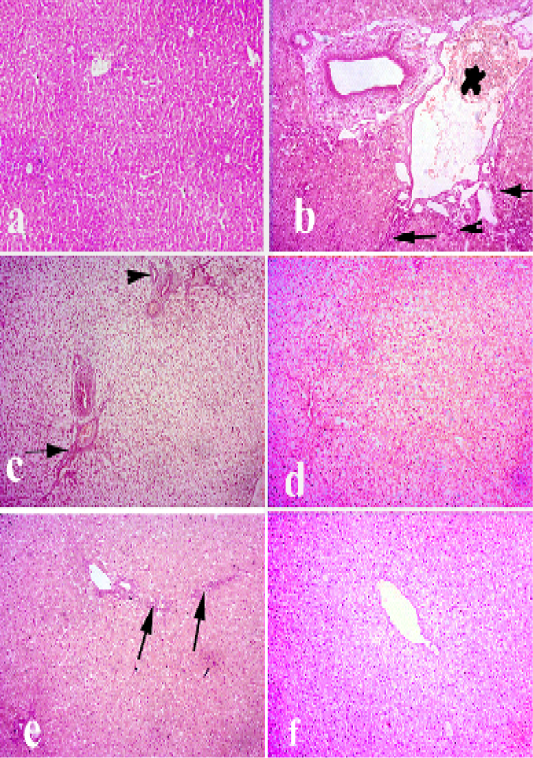

Liver of rabbit. (a) liver of control animals. (b and c) liver of pasteurella infected group showing degeneration. necrosis of hepatocytes and severe congestion of blood vessels, hyperplasia of bile duct and fibrosis. (d) livertreated with (Ofloxacin) showing diffuse vacuolar degeneration. (e) livertreated with grape seed extract showing mild vacuolar degeneration of hepatocytes along with fibrosis. (f) liver treated with (O+G) showing mild focal pericentral vacuolar degeneration. (arrows) refer to fibrosis and lymphocytic infiltrations, (arrow heads) refer to hyperplasia of bile ducts. Hematoxylin and eosin stain; magnification, 100×.